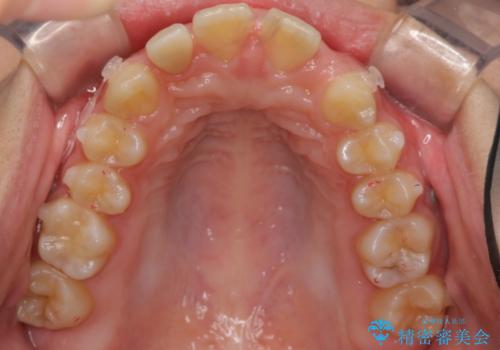

- 前歯の並びを主訴に来院。

前歯が出ており、また、左上の側切歯が1本生まれつき少ない状態でした。

今回は左右とも1歯対2歯の関係であるため、それは変えずに前歯を可及的にひっこめて足りない部分をブリッジで補う治療としました。

矯正後の前歯ブリッジについては横浜桜木町歯科の大元院長が担当しています。

奥歯の関係を完全に1級にするには右上の小臼歯の抜歯が必要でしたが、もともと左上の前歯が生まれつき少ないため今回は歯を抜かずに治療しています。